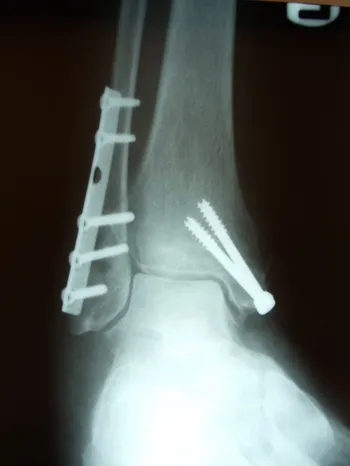

Xray and CT scan of displaced medial and posterior malleolar fracture with ORIF

Preop and Postop ORIF Posterior Malleolus Fracture with associated Fibular fracture